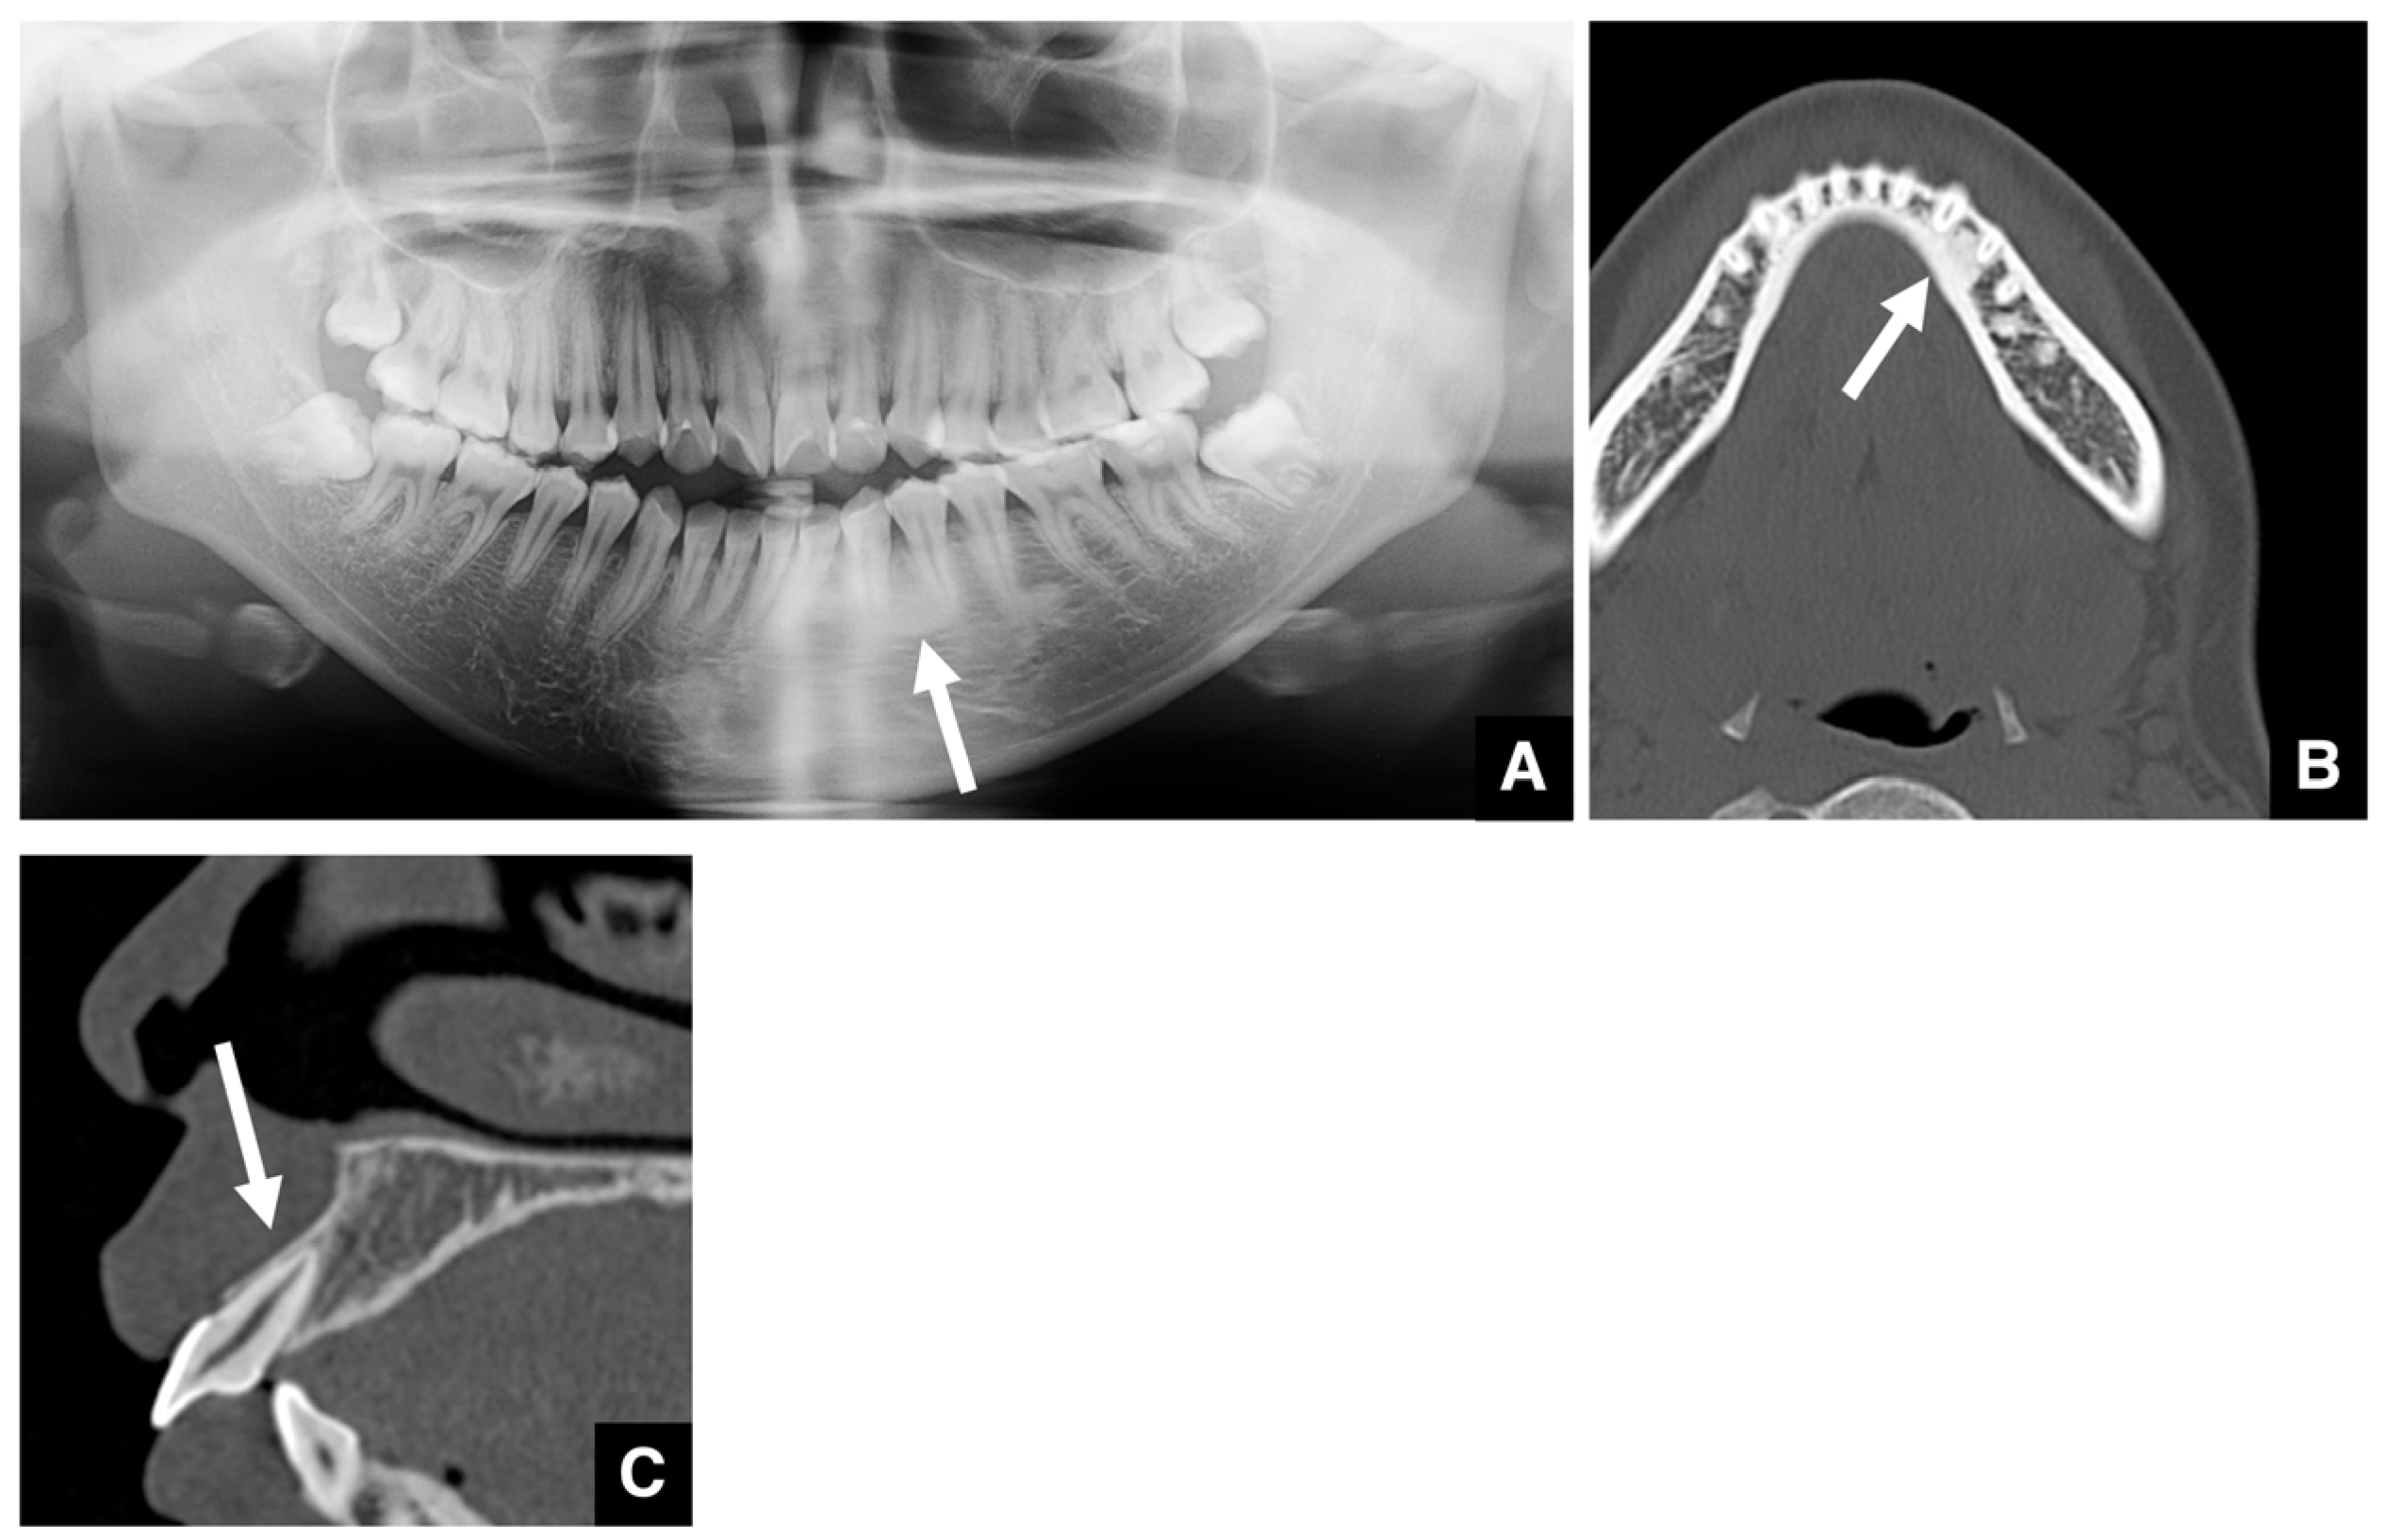

- Yoshioka, I.; Tanaka, T.; Khanal, A.; Habu, M.; Kito, S.; Kodama, M.; Oda, M.; Wakasugi-Sato, N.; Matsumoto-Takeda, S.; Fukai, Y.; et al. Relationship between inferior alveolar nerve canal positions at the mandibular second molar in patients with prognathism and the possible occurrence of neurosensory disturbance after sagittal split ramus osteotomy. J. Oral Maxillofac. Surg. 2010, 68, 3022–3027. [Google Scholar] [CrossRef]

- Yoshioka, I.; Tanaka, T.; Habu, M.; Oda, M.; Kodama, M.; Kito, S.; Seta, Y.; Tominaga, K.; Sakoda, S.; Morimoto, Y. Effect of bone quality and position of the inferior alveolar nerve canal in continuous, long-term, neurosensory disturbance after sagittal split ramus osteotomy. J. Craniomaxillofac. Surg. 2012, 40, 178–183. [Google Scholar] [CrossRef] [PubMed]

- Shah, N.P.; Murtadha, L.; Brown, J. Bifurcation of the inferior dental nerve canal: An anatomical study. Br. J. Oral Maxillofac. Surg. 2018, 56, 267–271. [Google Scholar] [CrossRef] [PubMed]

- von Arx, T.; Bornstein, M.M. The bifid mandibular canal in three-dimensional radiography: Morphologic and quantitative characteristics. Swiss Dent. J. 2021, 131, 10–28. [Google Scholar] [CrossRef]

- Aung, N.M.; Myint, K.K. Bifid mandibular canal: A proportional meta-analysis of computed tomography studies. Int. J. Dent. 2023, 2023, 9939076. [Google Scholar] [CrossRef]